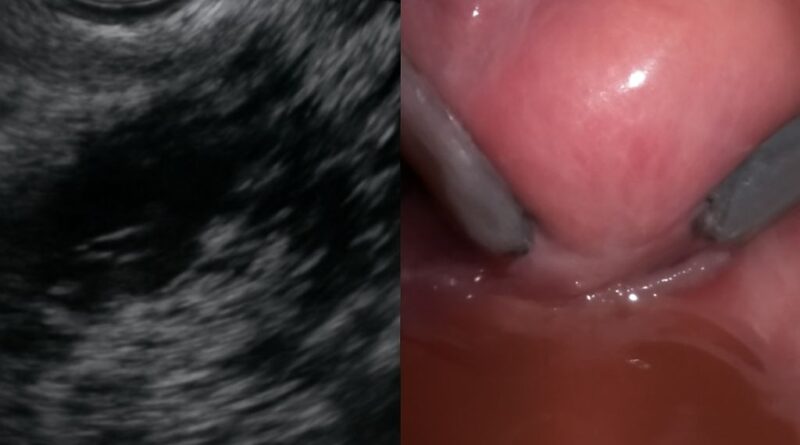

Read MoreNormal vs Abnormal Ovary Ultrasound: Reading Pelvic and Thyroid Scan Results Understanding normal vs abnormal ovary ultrasound results is one

Read MoreThyroid Ultrasound Images: What They Show and How to Read Them Ultrasound imaging of glandular and reproductive organs produces pictures

Read MoreAbnormal Uterus Ultrasound and Thyroid Cancer Ultrasound: What Imaging Shows Ultrasound imaging is used across many organ systems to evaluate